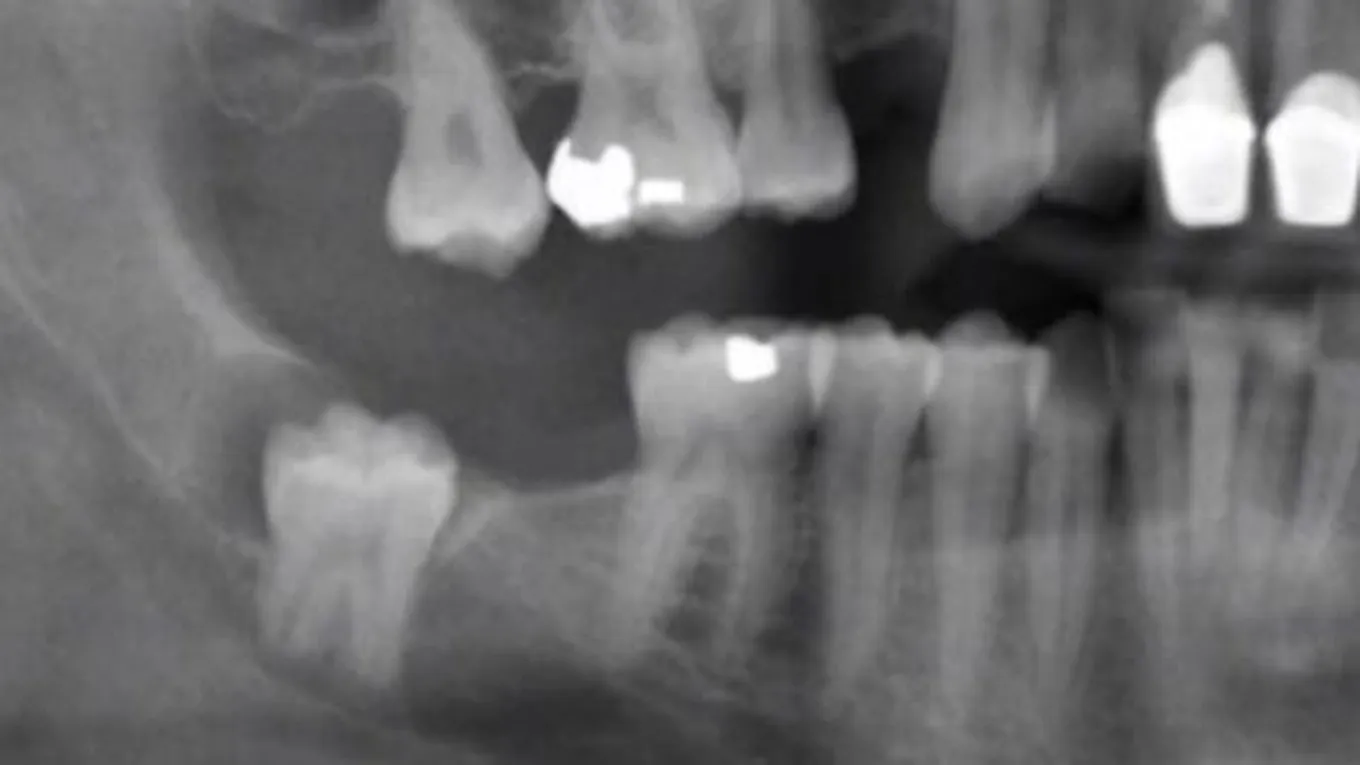

إن عدد الأضراس التي تظهر للإنسان الطبيعي هي أربعة ، اثنين بالفك السفلي واثنين بالفك العلوي وتظهر بأوقات مختلفة ضمن المرحلة العمرية الطبيعية التي تبدأ بها نمو الاضراس ولكن هناك بعض الحالات النادرة لنموها عند بعض الأشخاص وهي ظهورها كاملة بوقت قصير خلال سنة واحدة وبدون أي ألم وأعراض ومنهم من تتأخر لسن 35 تقريباً، يعتبر ألم الأضراس من الآلام الشديدة التي لا يستطيع الغنسان تحملها وتعود أسباب هذه الآلام لعم بزوغها بشكل صحيح بالفك حيث إنّه يطهر جزء منها أعلى اللثة والجزء الأكبر يبقى تحت عظام الفك وبهذه الحالة يحتاج لوقت طويل ليخرج ويبقى يسبب الوخز والألم من وقت لأخر.

- نمو ضرس العقل بشكل مائل أو غير عشوائي مما يسبب الكثير من الألم.

يظهر ضرس العقل كباقي الـأضراس بالفك سليمة وصحية ولكن بسبب ضيق الفك أثناء ظهورها تجعلها عرضة للتسوس والتلف حيث لأنها يمكن أن تنمكو بشكل مائل يؤثر على السن المجاور مما يؤدي بهذه الحالة للتخلص من الضرسين بسبب الألم الشديد الذي تسببه هذه الحالة، غير أنّ جميع الأشخاص يلجؤون لخلع ضرس العقل بسبب تسوسه الكبير لعدم القدرة على ادخال الفرشاة لأخر الفك مما يؤدي لتجمع بقايا الطعام وهي البيئة المناسبة لنمو البكتيريا التي تسبب العديد من الاتهابات بالفم وتسوس الأضراس، يتم خلع أضراس العقل بشكل طبيعي عند طبيب الأسنان بحالة ظهور نسبة كبيرة منه أما بحالة عدم ظهوره وبقائه نامياً تحت اللثة فيتم إجراء جراحة لخلعه عن طريق عمل شق صغير من ثم خلع الضرس ويتم المعالجة بعد ذلك بتناول المسكنات وتناول المثلجات لوقف النزيف وبعض المضادات الحيوية.